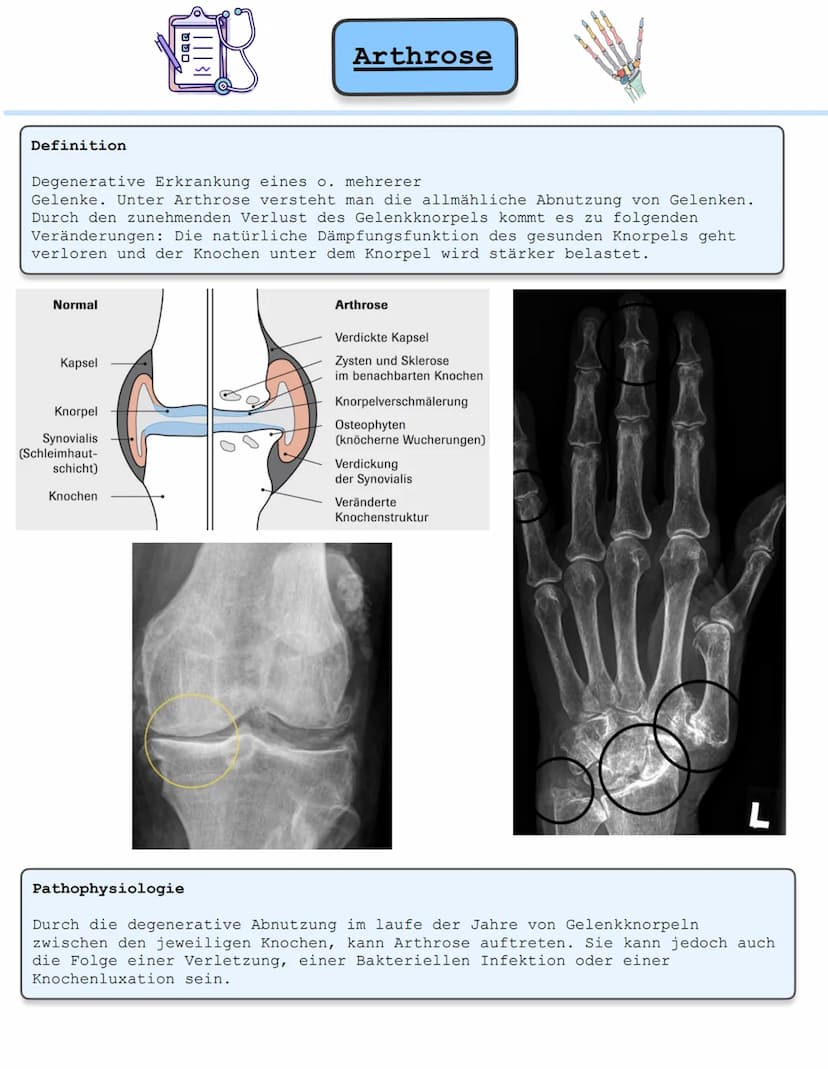

Arthrose ist eine degenerative Gelenkerkrankung, bei der sich die Gelenke nach und nach abnutzen. Der Gelenkknorpel wird dabei immer dünner und verliert seine natürliche Dämpfungsfunktion.

Wenn der schützende Knorpel verschwindet, reiben die Knochen direkt aufeinander. Das führt zu verschiedenen Veränderungen: Die Gelenkkapsel verdickt sich, es entstehen knöcherne Wucherungen (Osteophyten) und der Knochen unter dem Knorpel wird geschädigt.

Ärzte stellen die Diagnose durch Röntgenbilder, die eine Verschmälerung des Gelenkspalts und knöcherne Veränderungen zeigen. Zusätzlich werden oft Ultraschall, MRT oder Blutuntersuchungen gemacht.